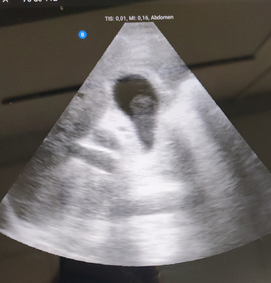

ECOGRAFIA CLÍNICA: Se aprecia vesicular biliar bien repleccionada con imagen en su interior redondeada, hipoecoica, sin sombra, Murphy ecográfico positivo.

Lo llamativo para mi del caso fue visualizar un calculo biliar sin sombra (calculo blando) , saber de su caracteristicas ecograficas y tenerlo como opción diagnóstica.